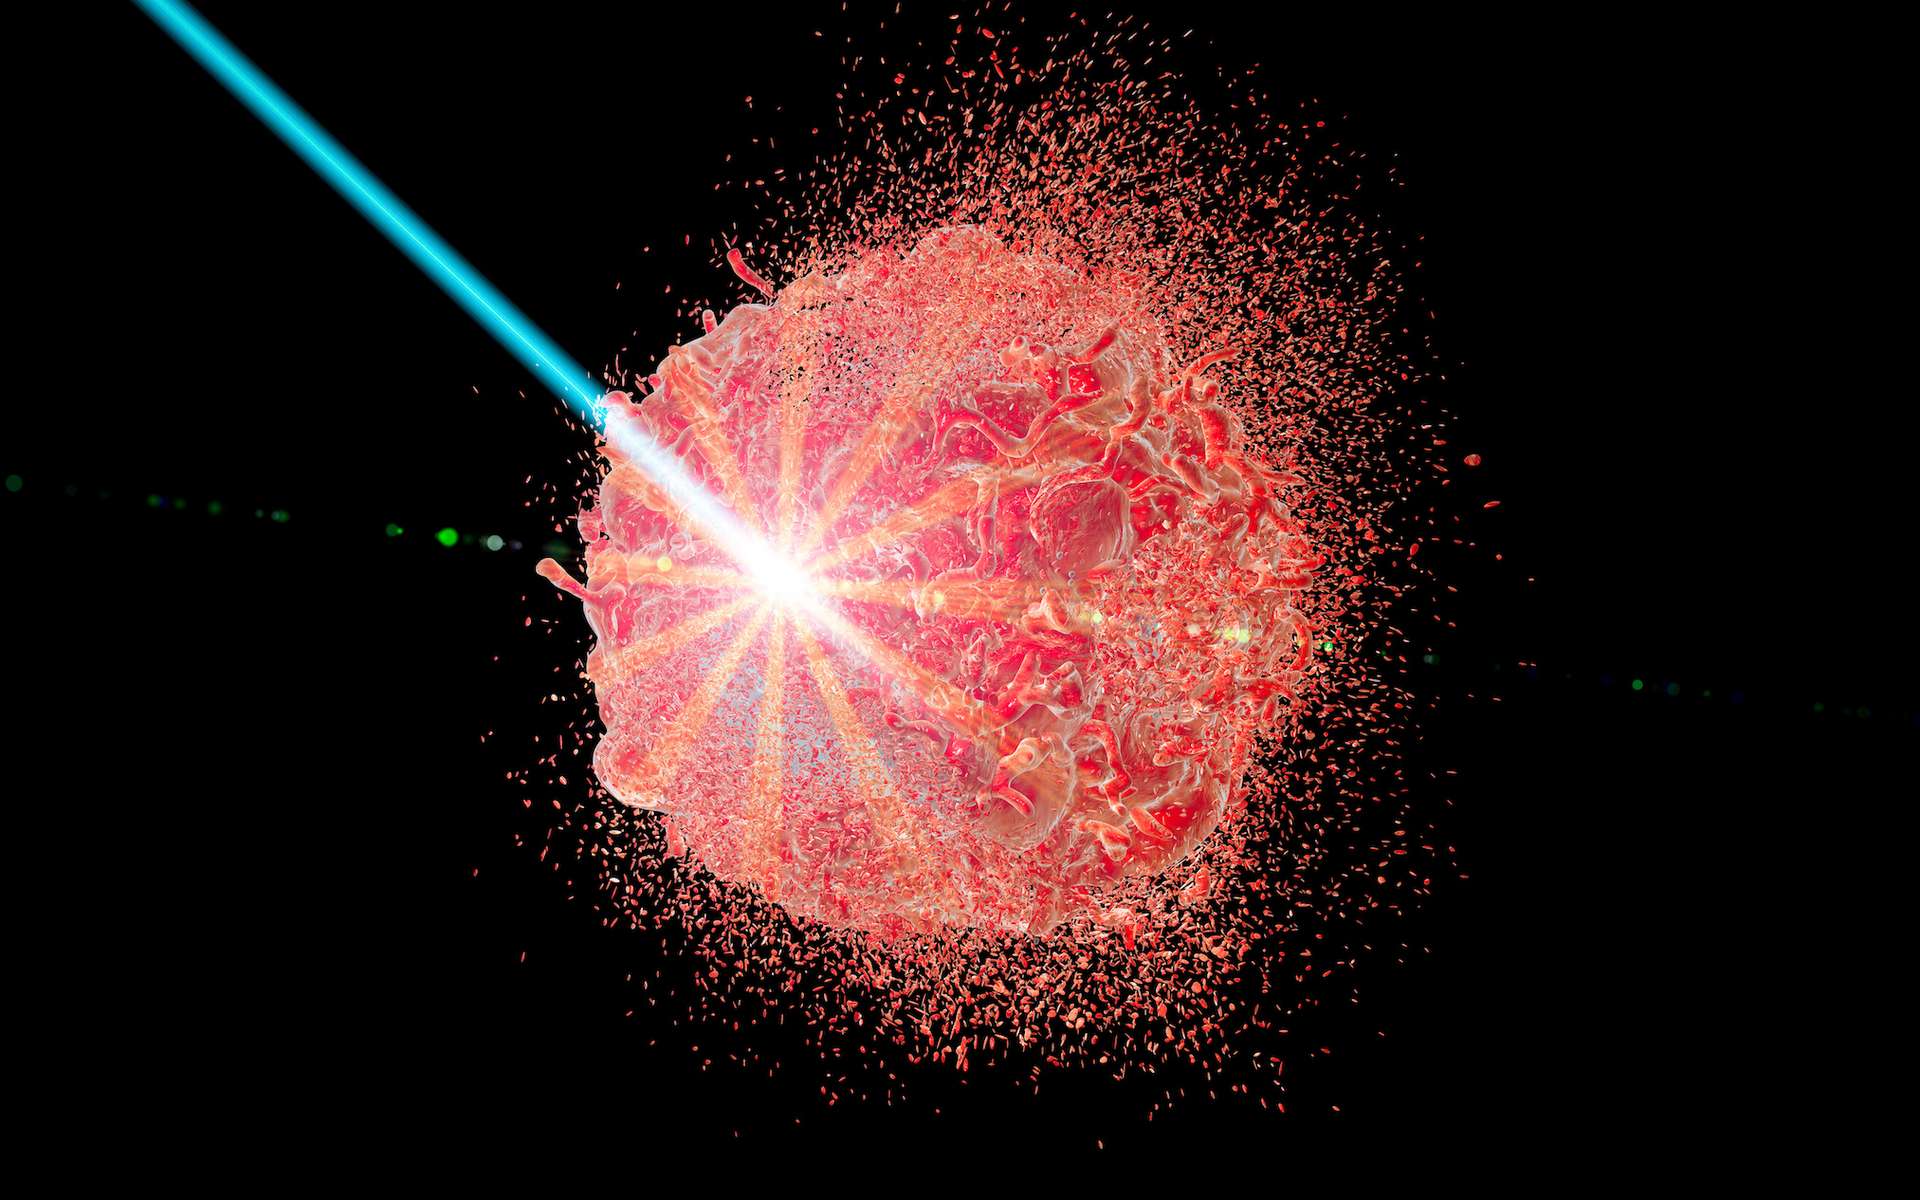

Les traitements contre le cancer ont longtemps été entravés par la capacité des cellules cancéreuses à développer une résistance aux médicaments. Cependant, une récente percée scientifique offre un nouvel espoir en piratant l’évolution même des cellules tumorales pour les rendre vulnérables aux thérapies. Cette approche novatrice, développée par des chercheurs de l’Université d’État de Pennsylvanie, […]

Les traitements contre le cancer ont longtemps été entravés par la capacité des cellules cancéreuses à développer une résistance aux médicaments. Cependant, une récente percée scientifique offre un nouvel espoir en piratant l’évolution même des cellules tumorales pour les rendre vulnérables aux thérapies. Cette approche novatrice, développée par des chercheurs de l’Université d’État de Pennsylvanie, […]